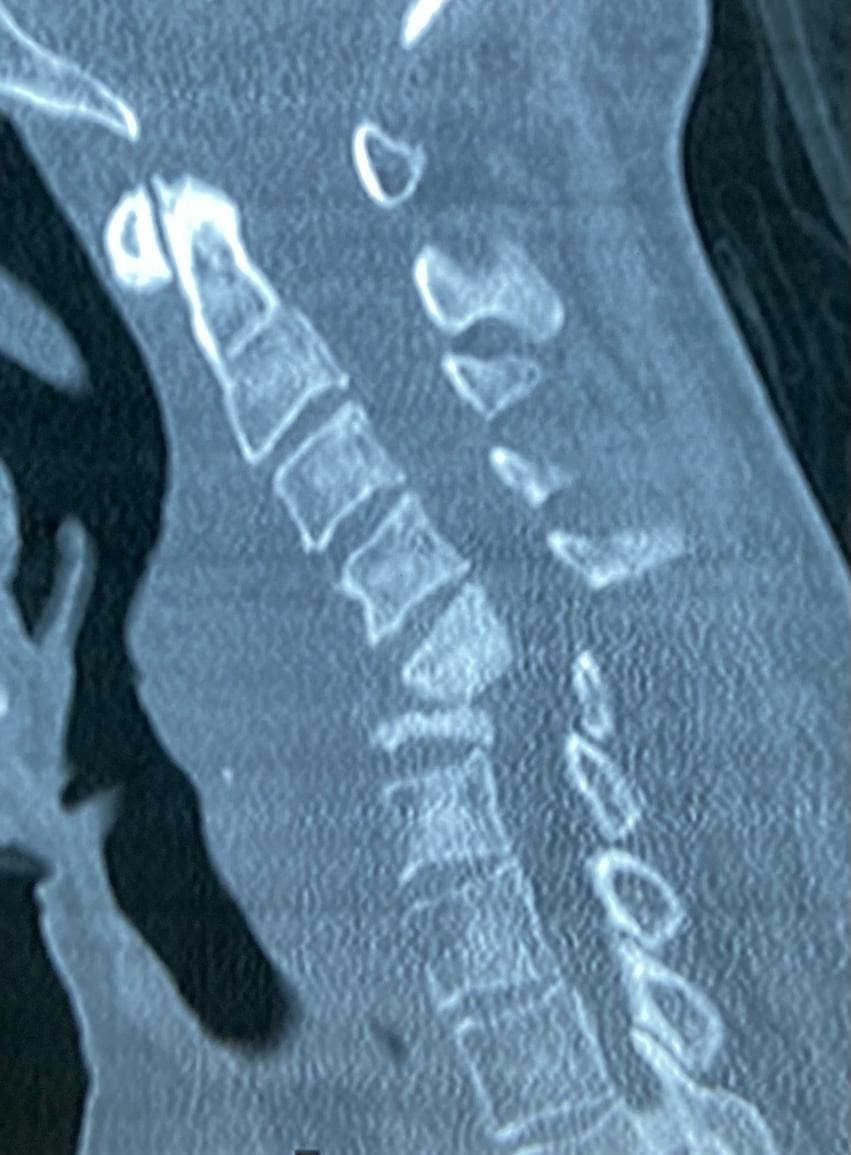

A 65-year-old lady came to us with severe weakness in all four limbs. She was unable to move her hands or legs and had gradually lost her independence. Investigations, including MRI, revealed collapse of the C5 and C6 vertebral bodies due to spinal tuberculosis. A large epidural abscess was pressing on her spinal cord, leading to quadriplegia (paralysis of all four limbs). It was a critical situation, as without urgent treatment, the chances of recovery were very slim. After careful evaluation, we planned an anterior cervical corpectomy of C5 and C6, removal of the diseased bone and abscess, and reconstruction with a bone graft from her iliac crest along with a plate for stability.